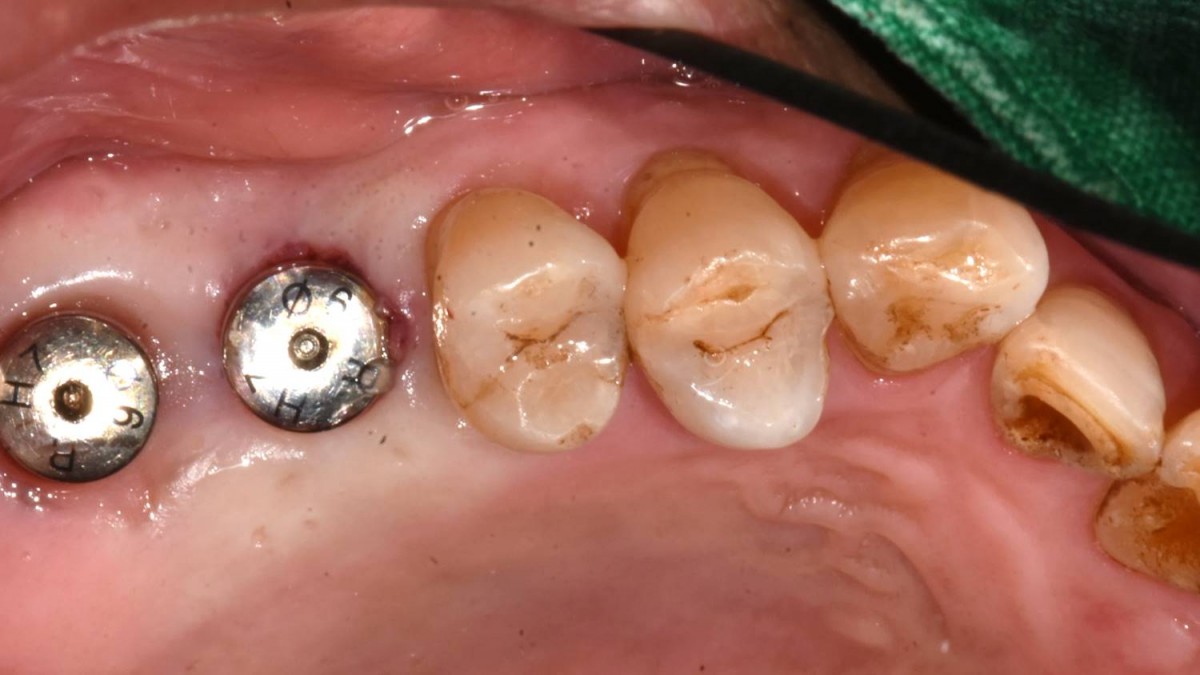

Maxillary Sinus Graft, 2 Implants, Crown Contouring

<GCaks> A 56-year-old male patient had pain-inducing caries, and perio-involved tooth mobility resulted in a tooth fracture at 1st molar. And it was removed months ago. He was a heavy smoker and showed poor oral hygiene.